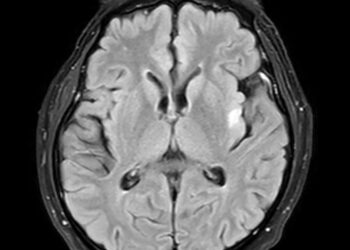

Skaityti daugiauDetailsNokardiozė yra bakterinė infekcija, kuri gali pažeisti plaučius, odą ar net smegenis. Žmogus šia liga užsikrečia įkvėpęs Nocardia bakterijų arba...